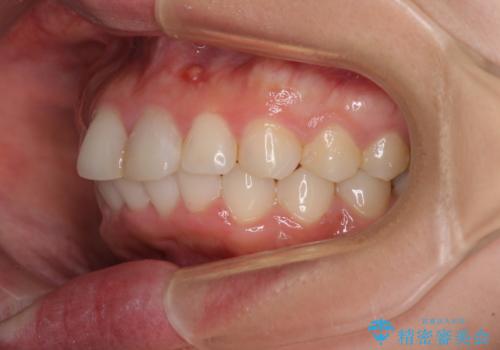

矯正治療の後戻り ガタガタになった前歯の部分矯正

- 以前の矯正治療の後戻りを気にして来院された患者様です。

下顎前歯にデコボコがあるため、ワイヤー矯正により改善することとしました。